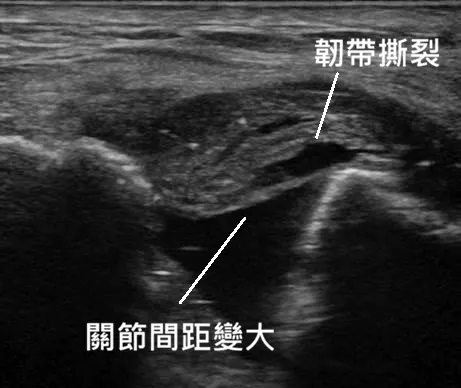

1. 精準診斷:高解析超音波

X 光只能看骨頭位置,確認有無骨折及移位,超音波才能真正看到韌帶有沒有斷! 醫師會利用動態超音波,觀察關節是否不穩定地開合,並觀察韌帶撕裂的狀況與積水情形。